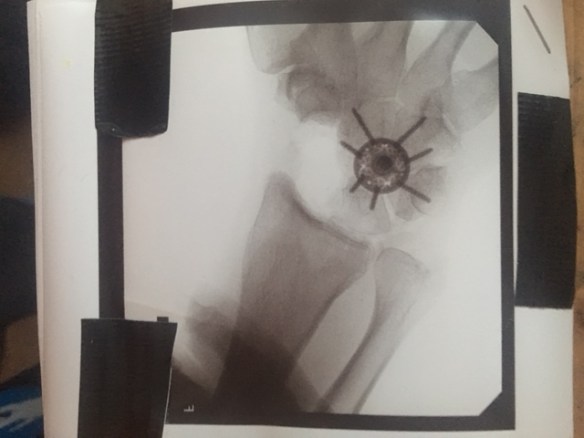

Wednesday January 4th at around 1:pm I went under. I did not witness the surgery, thankfully I saw no knives, no blood, heard no crunching of bones or whirling of drills. I simply woke up groggy and fuzzy, my hand wrapped up in a splint, thick with padding and ace bandages. There was still no pain, the nerve block was totally effective. No evidence of that major reconstruction, just my big fat pink fingers poking out.